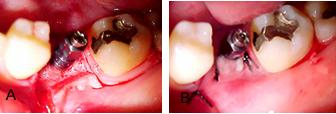

Figuras 4 a e b.

Figura 4 a, mosta o osso alveolar neoformado, 7 meses após a extração e ROG. Feito retalho para colocação do implante na área do 36. Como pode-se ver, o osso alveolar estava perfeitamente reconstruído e o aspecto da área era excelente. Assim foi sugerido ao paciente a colocação de um implante Conect, isto é, um implante onde seria possível colocar uma coroa imediata no implante. As moldagens foram tiradas conforme veremos, encaminhadas ao laboratório para confecção do guia cirúrgico e demais procedimentos.

A figura 4b, mostra o início da cirurgia, com os retalhos totais levantados. Dois aspectos devem se observados nesta fotografia. Primeiro, o osso alveolar formado com a ROG, que está em condições excepcionais.

Figuras 5 a e b.

Figura 5a, mostra a cavidade óssea pronta com as brocas convencionais, isto é, usou-se inicialmente a broca chama até a profundidade de 11mm aproximadamente, depois a broca de 2mm, seguindo a seqüência: 2,8mm e 3,0mm.

Figura 5 b, a cavidade terminada onde usou-se no término a broca do Kit cirúrgico do Conect, para o implante que foi colocado de Ø4,3 X 10,0mm. Todos esses procedimentos têm que ser realizados com muita cautela e com as brocas irrigadas abundantemente com soro fisiológico.

Figuras 6 a e b.

Figura 6a, mostra o implante colocado até o ponto em que o motor de implante, com um contra-ângulo de 1:252 de redução levou o implante Conect até se desarmar, isto é, admitimos que neste ponto o torque foi de aproximadamente 30 N, para o término da ancoragem precisamos de 50N, assim na fotografia 6a, estamos removendo o monta implante para terminar a ancoragem, parafusando com uma chave própria do Kit cirúrgico, de aço, mais resistente, para levarmos o implante até a ancoragem completa, realizada com uma chave catraca, que dará aproximadamente os 50N necessários a perfeita ancoragem deste tipo de implante.

Nota: É impressionante o grau de fixação que os implante Conect atingem, por mais

manipulados que sejam durante os procedimentos protéticos, eles absolutamente não se alteram, dando ao protesista toda liberdade de ação para realizar as coroas.